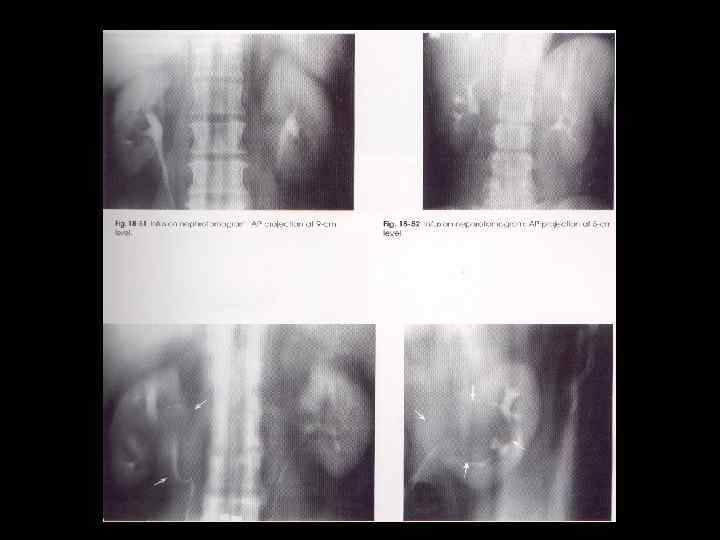

Nephrotomography • Best method for visualizing renal parenchyma (neprons and collecting tubules) • Ability to visualize kidneys free of intestinal content superimposition

IVU Procedure cont’d • Tomograms are obtained once bladder is filled – Pt is measured, divide number by 3, cuts begin there • Pt. measures 30 cm, beginning cuts at 10 cm • Release compression slowly • Have pt void, and obtain post-void film